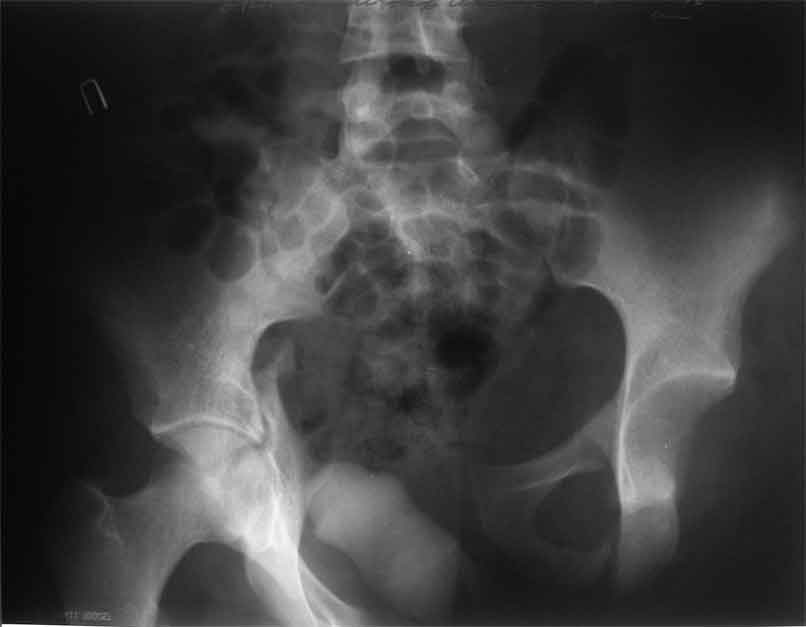

продолжение темы. не увидел энтузиазма в обсуждении. Вопросы прежние, первым этапом закрыто устранили вертикальное и передне-заднее смещение. Каким образом восстановить целостность тазового кольца, из каких доступов? Снимки в приложении

передне-неружным внебрюшинным доступом к лонно-седалищномц сочленению - синтез штангами(можно из заднего доступа, но хуже обзор и труднее репозиция), из этого же доступа к крыше вертлужной впадины - синтез реконструктивными пластинами(мы делали "ChM" тазовыми, хорошо себя зарекомендовали), передним доступом на лонное сочленение - синтез подобной пластиной. к задней колонне вертлужной впадины - задне-наружный доступ, синтез такой же пластиной. КРОВОПОТЕРЯ!!! возможно до 7л. мощная ангтибак. профилактика во время и после операции. до перехода на заднюю колонну оперировать в аппарате. бвл подобный случай, по снятии аппарата через 8 мес. - рецедив смещений сразу.